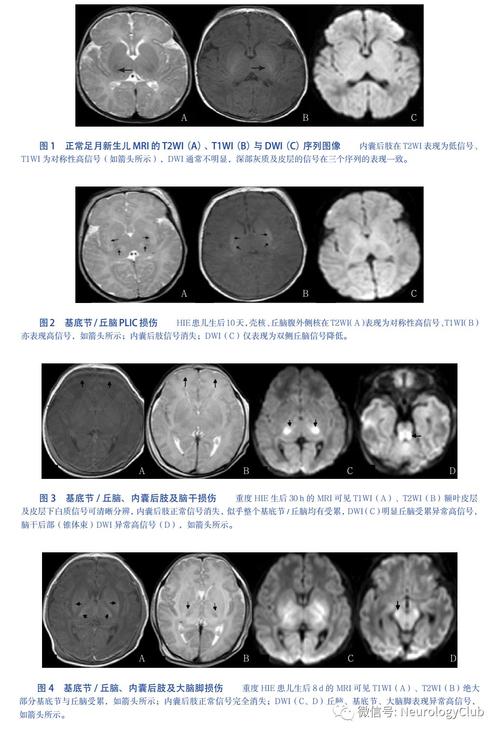

- 磁共振成像(MRI): 这是评估脑损伤程度的“金标准”,它能更清晰地显示大脑不同区域的损伤情况,对于轻度HIE,MRI通常显示正常或仅有非常局灶、轻微的异常。